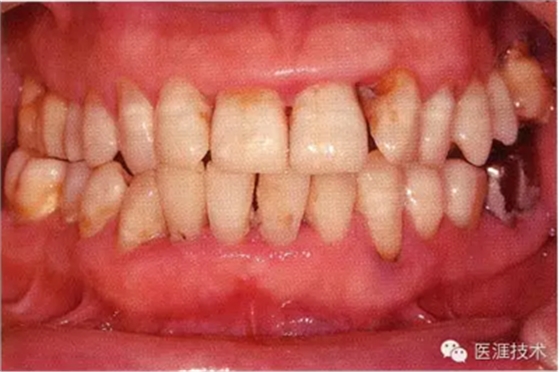

55歲牙周炎男性的臨床照片

55歲男性抽煙患者(1天20支、抽煙35年)。菌斑控制得不好。通過(guò)牙周探診,全頜有4~9mm的牙周袋,有1~3度的根分叉部病變。通過(guò)X光片觀察,上頜前牙中度牙槽骨吸收,其他地方有中度牙槽骨吸收。受吸煙影響,牙齦纖維性肥厚,呈紅黑色。牙齦幾乎沒(méi)有浮腫和發(fā)紅,所以這個(gè)病例是從外觀上無(wú)法預(yù)測(cè)病癥嚴(yán)重程度的病例。